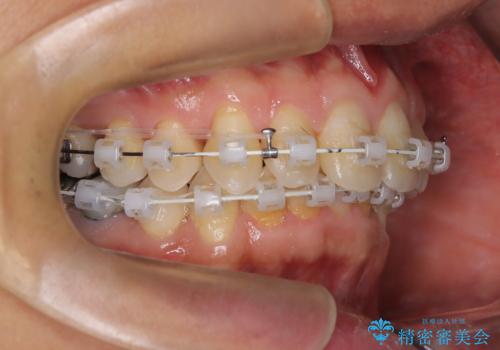

- 矯正装置

- 審美装置

上顎はリンガルアーチにて遠心移動を行うことで前歯を唇側傾斜させずに配列することができました。